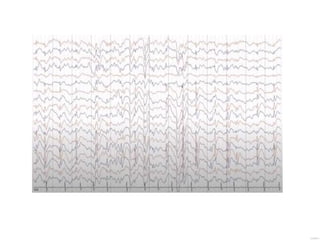

EEG persistent burst-suppression pattern

during both the awake and sleep states

burst-suppression pattern during the sleep

EEG hypsarrhythmia, multifocal or focal epileptiform

discharges

EEG generalized 3 Hz to 4 Hz spike-and-wave

IPS triggers generalized spike-wave in 15%

hyperventilation

EEG Continuous, slow (<2 HZ spike-wave in >50% of non-REM

sleep)

EEG 5 Hz to 9 Hz theta to alpha frequency range, maximally present at

the anterior temporal region

EEG Hemispheric slowing and interictal discharges